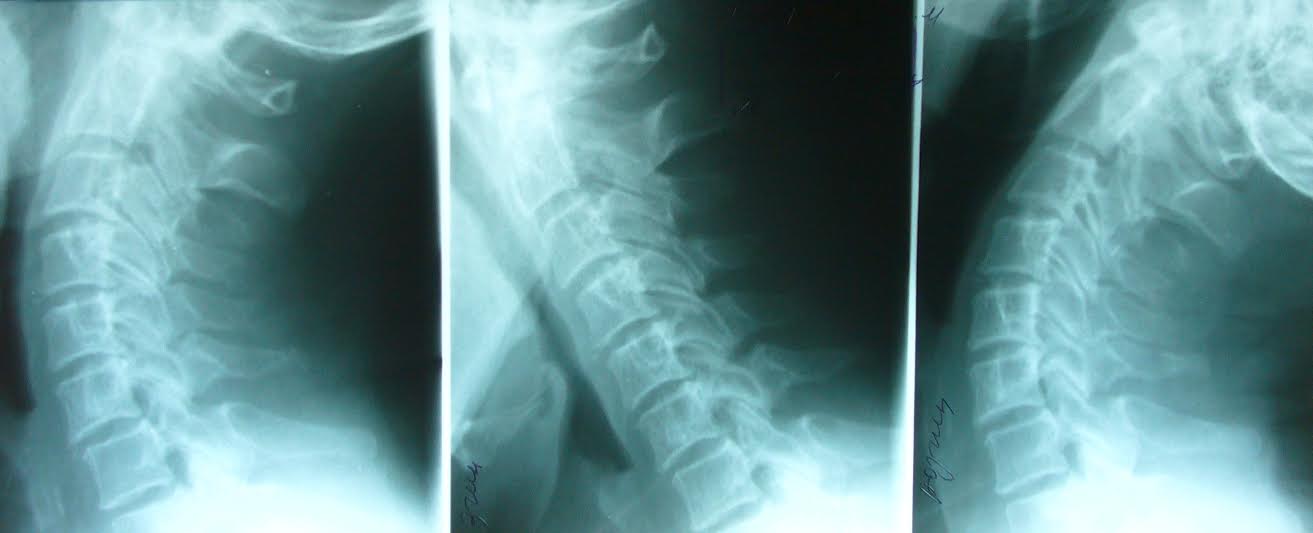

Рентгенографія показує рентгенівське зображення хребта і міжхребцевих суглобів в двох площинах, а комп’ютерна томографія – тривимірне зображення, тобто лікар бачить об’ємний орган, не тільки кісткову систему, але й стан м’якотканинних утворів. Дуже важливим у хребті є стан міжхребцевих дисків, наявність можливих гриж або протрузій останніх.

«Перевага рентгенографії в центральній міській клінічній лікарні полягає в тому, що ми володіємо технологіями виконання функціональних рентгенівських обстежень. В цьому наша унікальність. Рентгенографія хребта може бути в стані повного згинання, у звичайному положенні і в стані повного розгинання. Отримуючи ряд функціональних зображень, лікар-рентгенолог практично безпомилково може визначити наявність або відсутність і навіть вид патології хребта. Іноді люди хочуть провести обстеження цілого хребта, а це не зовсім правильно. Обстеження робиться по вказівках лікаря і лише у певних відділах для того, щоб опромінення не було занадто великим для людини і не несло шкоди.

Що стосується комп’ютерної томографії, то унікальність нашої клініки полягає в тому, що тут теж неодноразово проводилися функціональні обстеження хребетного стовпа та інших органів і систем. Це можна назвати навіть зображенням 4D – коли лікар бачить об’єм і функцію, як себе «поводить» той чи інший суглоб, коли він повністю розігнутий чи зігнутий і знаходиться в звичайному стані», – каже Ігор Соколовський.